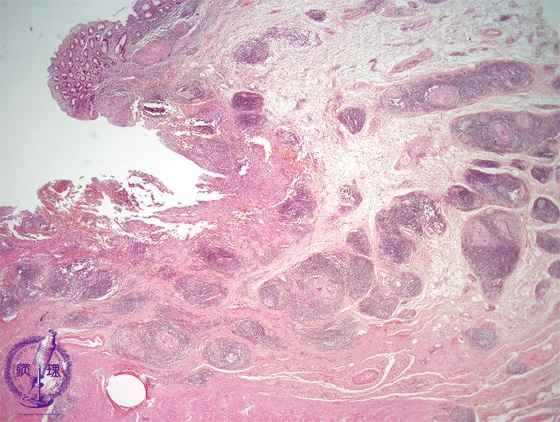

Microscopic view (H&E stain, low power): Multiple caseating granulomas are seen forming in the bed of an ulcer which shows characteristic undermined edges.

Click the image to see the enlarged image.